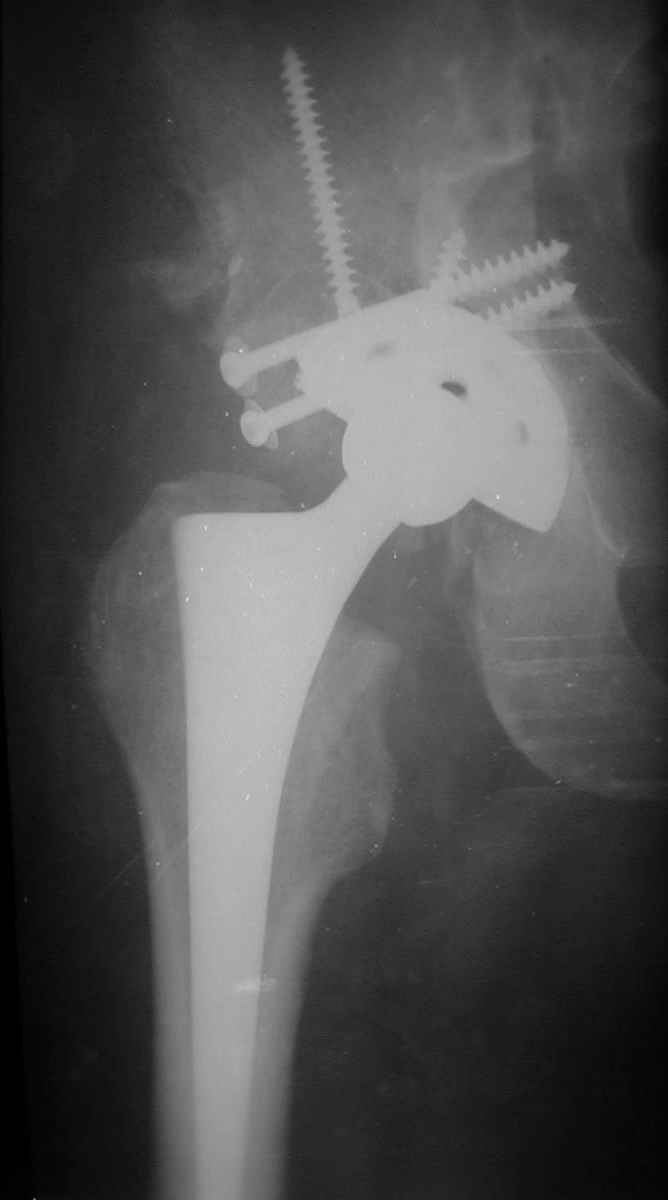

В институте совместно с фирмой Зиммер достаточно регулярно (практически ежемесячно) проводятся 2-х недельные циклы по различным вопросам эндопротезирования. Если есть возможность и желание, мы готовы поделиться с Вами нашим опытом, тем более есть что показать и что обсудить - в настоящее время ежедневно выполняется от 6 до 10 эндопротезирований коленного и тазобедренного сустава. В качестве примеров хочу показать 2 наблюдения, через 1 год и 5 лет после операции

5 лет